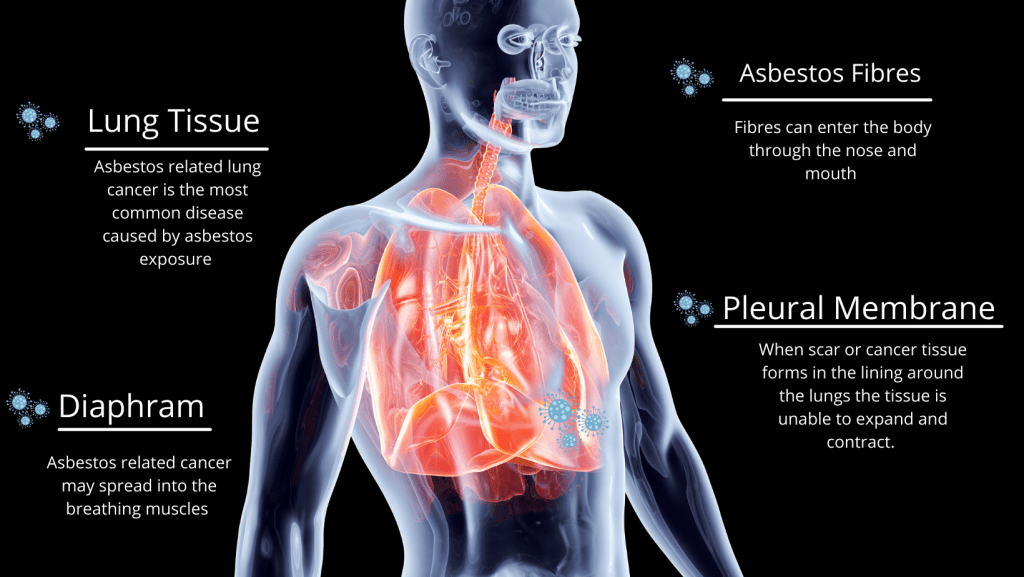

A progressive lung scarring disease caused by inhaled asbestos fibres lodging in alveoli and small airways, resulting in stiff lungs and reduced oxygen transfer.

Changes in the lining of the lung (pleura) rather than the lung tissue itself. These may show up as pleural thickening, effusions or plaques (areas of scar tissue/calcification).

Lung cancer

- A rare but aggressive cancer of the membranes lining the lungs (pleura) or abdomen (peritoneum) almost exclusively linked to asbestos exposure.